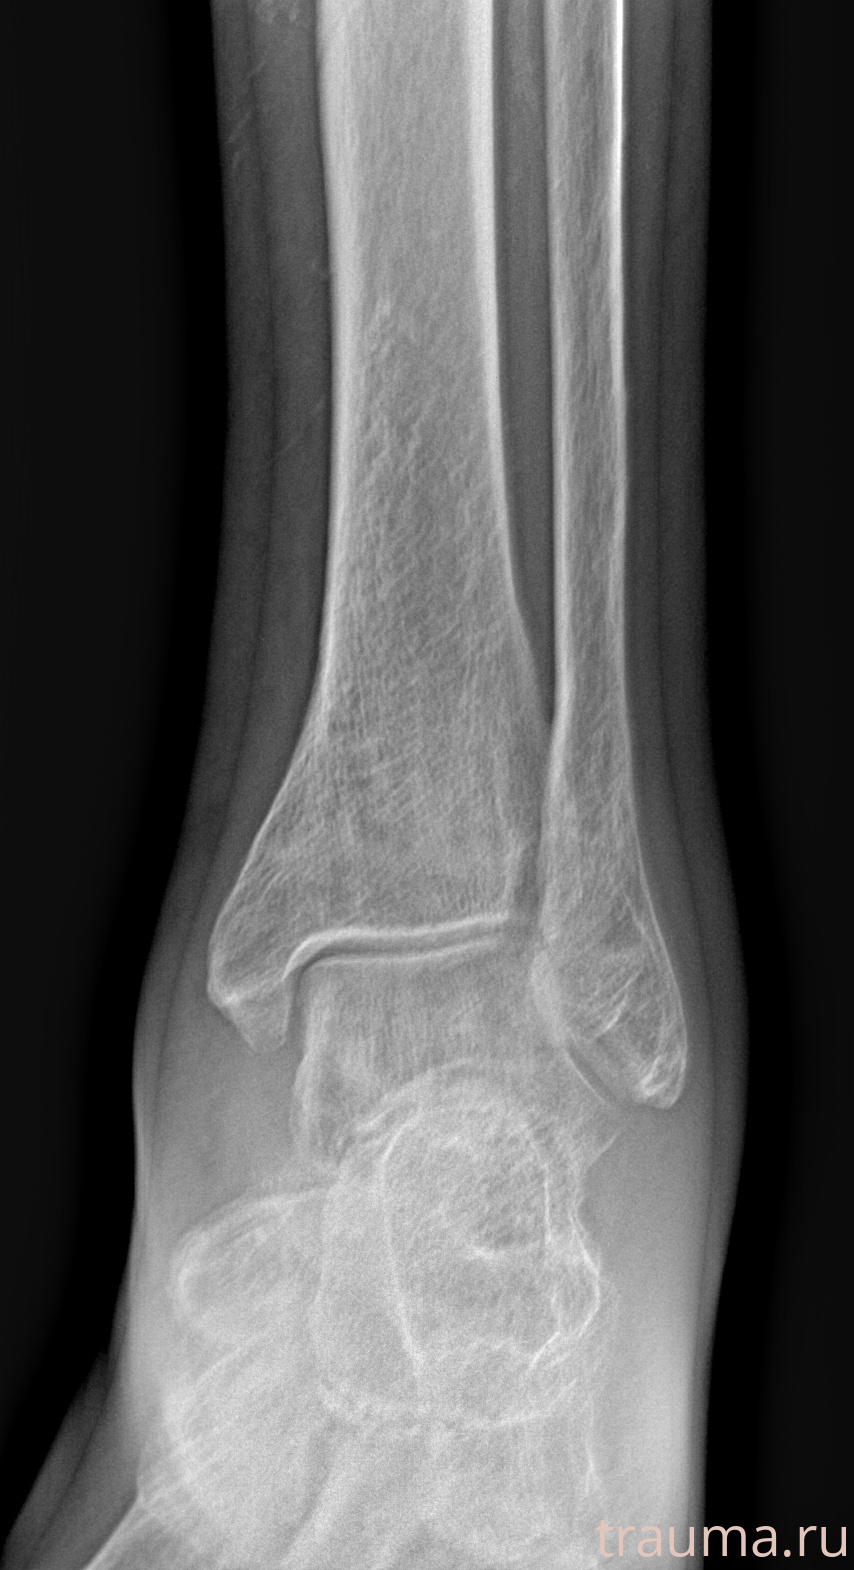

Рентгенограммы

Рентген на дому: по вашему адресу приезжает врач-рентгенолог, травматолог-ортопед с мобильным рентгеновским аппаратом, проводит диагностику травмы или заболевания, делает необходимые рентгенограммы, дает рекомендации по дальнейшему лечению. Получить качественные снимки в домашних условиях возможно благодаря уникальной методике, разработанной МосРентген Центром для института  Склифосовского